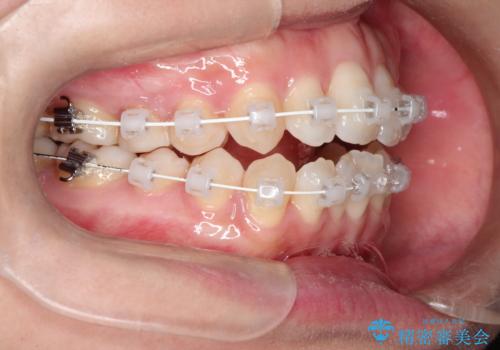

前歯がガタガタで咬めない ワイヤーによる抜歯矯正で整った歯並びへ

- 前歯がガタガタなのと、前歯でものが噛めないことを主訴に来院されました。

前歯の叢生があり、上下の前歯が接触していない開咬という状態でした。

左側の上下の前から4番目の歯を抜歯して、矯正することとしました。

装置は表側のワイヤーを選択されました。

ガタガタがなくなり、上下の前歯が接触すようになり、見た目とともに咬みやすくすることができました。